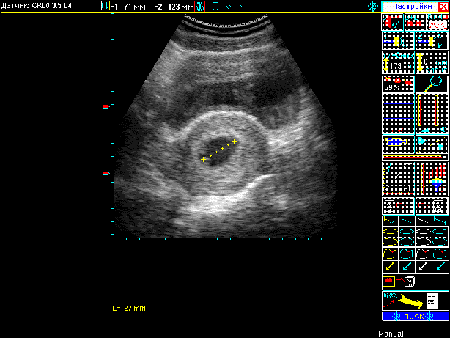

Примеры того, как выглядит экран при различных режимах сканирования можно увидеть в Таблице 4.

Таблица 4. Общий вид экрана в различных режимах сканирования.

| Вид экрана | Режим сканирования |

|---|---|

![]() |

Режим В |